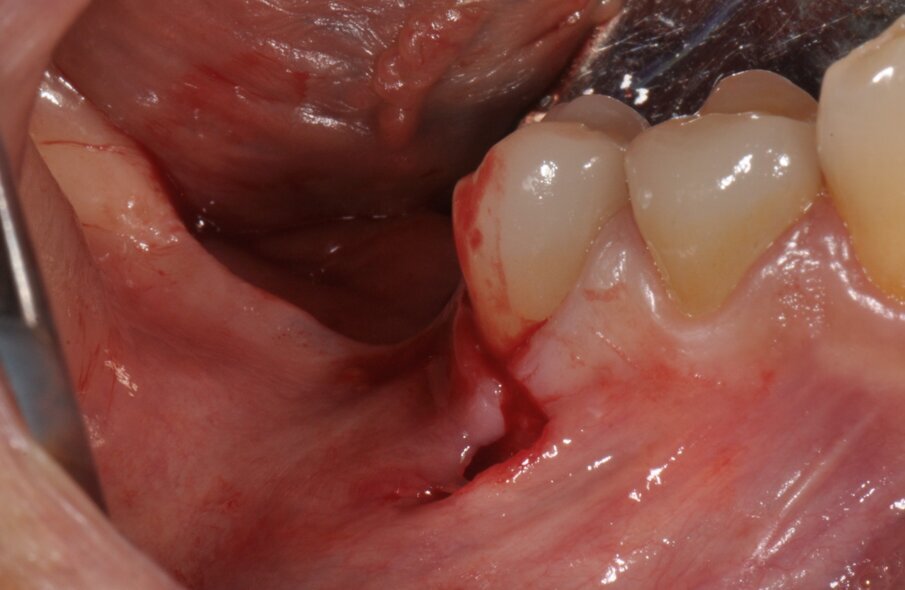

Figg. 3, 4_Come previsto dalla procedura di GBR Pocket Technique, si esegue un’incisione minimamente invasiva con estensione vestibolare e linguale.